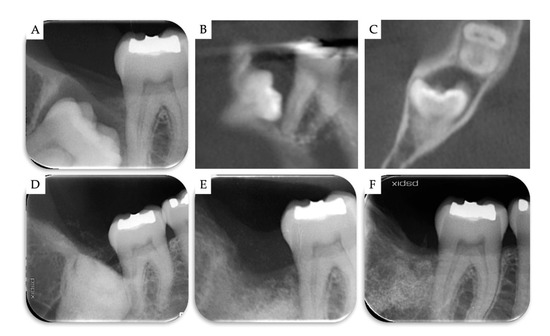

3. Results